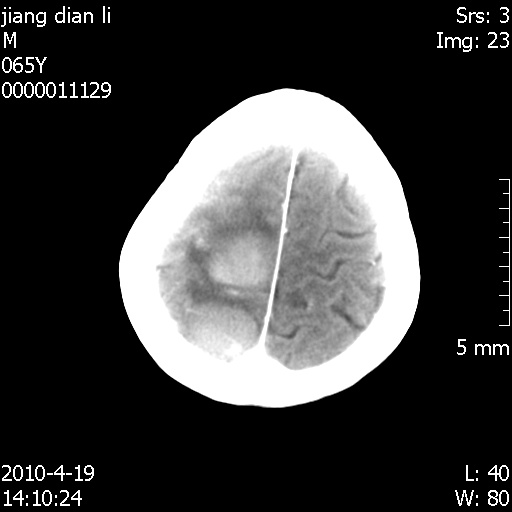

今天上班后发现病人前天复查(4月18日发病,19日初诊,22日复查),三个病灶均明显增大,边缘仍旧清楚,水肿加重,右侧脑室基本闭塞。

基于这样的表现,不知大家有什么看法?(临床其他检查我还没有追踪)

我想:如果是肿瘤出血的话,一般不会导致体积明显改变,水肿又进一步加重;如果是出血灶,那么现在应该正好是水肿加重的时候,还是比较符合,但是为什么边缘又是这样的特点?

遗憾! 复习了复查片:发现顶叶出血灶破入侧脑室,侧脑室体部见少许高密度。